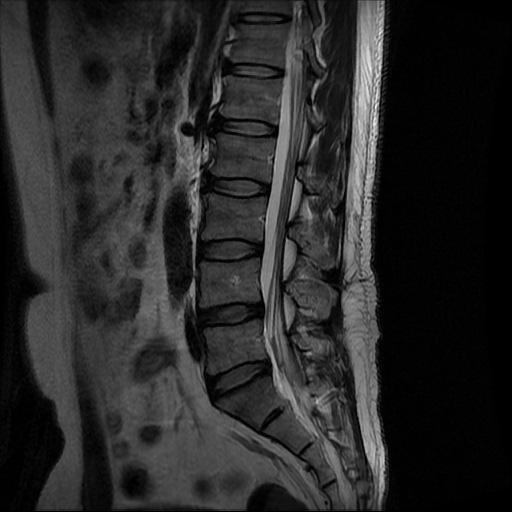

우선 현재로썬 사진만으론 판단을 하기에 제한이 되지만 사진상 디스크 상태는 심해보이지 않습니다.

요추부위의 하부 에서 약간의 팽윤이나 돌출로 의심해볼수 있는 정도이지만, 정확한 상태는 관련 전문의에게 진료시 문의를 하시는 것을 추천드립니다.